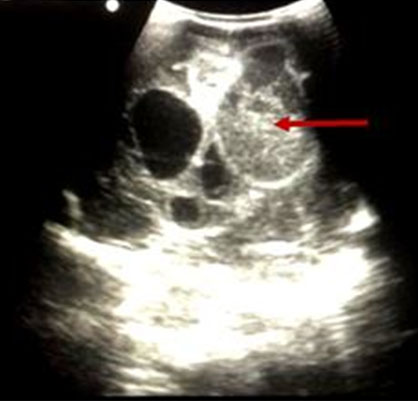

She subsequently had right fronto-parieto-temporal craniotomy and ultrasound-guided right occipital abscess aspiration (see Figure 3 and Figure 4). The eloquent areas of the brain were avoided.

Figure 3: Coronal ultrasound image of the similar patient with the abscess cavity (red arrow) seen compressing the lateral ventricle. Associated dilatation of the contralateral ventricle is noted due to hydrocephalus.